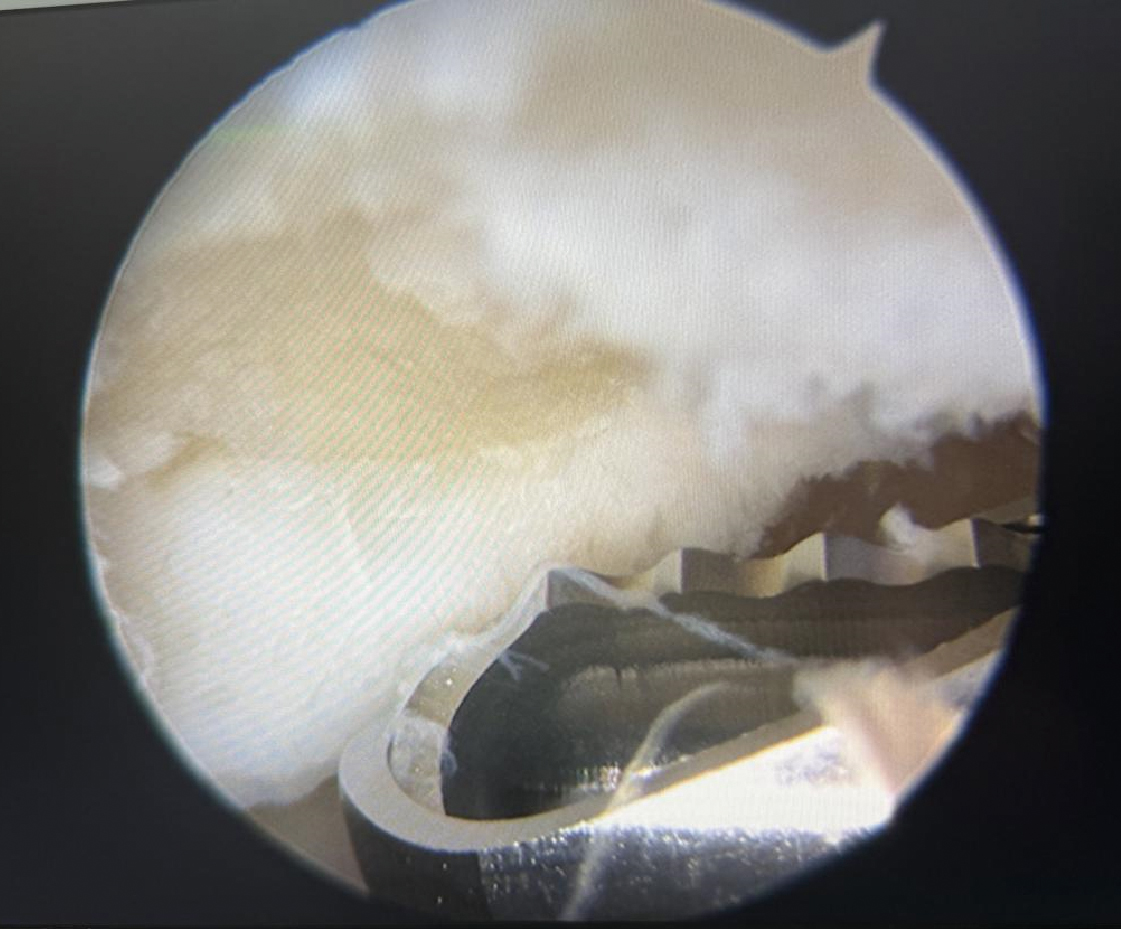

图2

关节镜下支架放置手术操作过程"